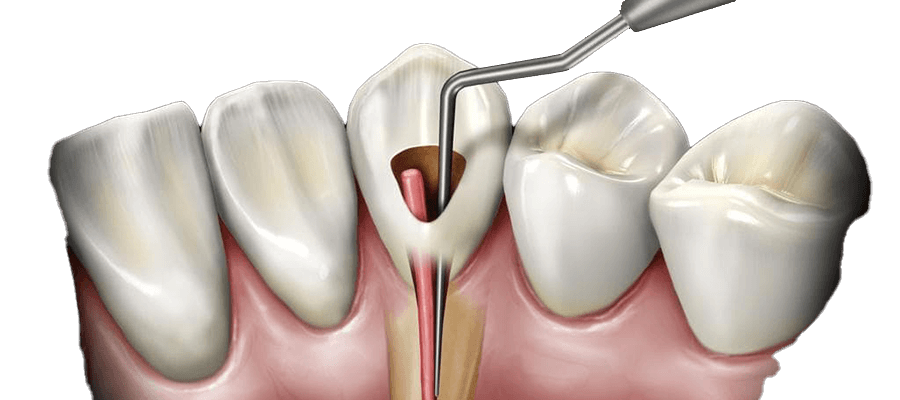

عصبکشی یا اندودنتیک یک روش درمانی است که برای درمان عفونت یا آسیب به عصب دندان (پالپ) انجام میشود. در این فرآیند، بافت آسیبدیده یا عفونی از داخل دندان خارج شده و فضای خالی با مواد مخصوص پر میشود. هدف از این درمان حفظ دندان و جلوگیری از نیاز به کشیدن آن است.

- مرحله سوم: دسترسی به پالپ

پس از بیحسی، پزشک با استفاده از ابزارهای مخصوص، به بافت پالپ دندان دسترسی پیدا میکند. این کار معمولاً از طریق ایجاد یک سوراخ کوچک در سطح دندان انجام میشود.

- مرحله چهارم: خارج کردن بافت آسیبدیده

در این مرحله، بافت پالپ آسیبدیده یا عفونی با استفاده از ابزارهای خاص خارج میشود. این کار باید با دقت انجام شود تا هیچ بخشی از بافت عفونی باقی نماند.

- مرحله پنجم: تمیز کردن کانالها

پس از خارج کردن بافت پالپ، کانالهای ریشه دندان تمیز و ضدعفونی میشوند. این کار برای جلوگیری از عفونتهای بعدی ضروری است.